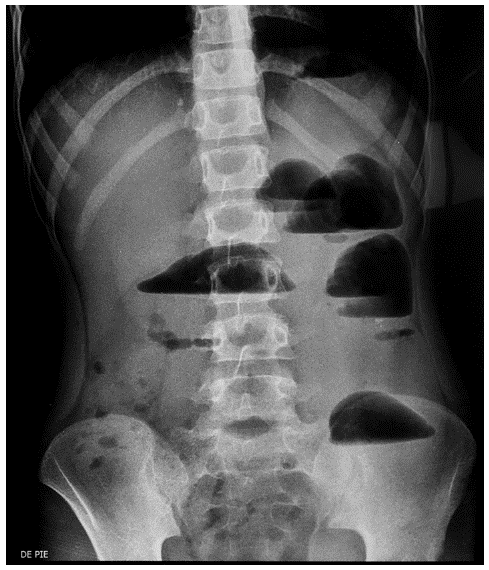

Varón de 6 años, que fue valorado por el cirujano pediatra en el Servicio de Emergencias debido a vómito bilioso persistente, acompañado de dolor y distensión abdominal de 48 horas de evolución. El peso al ingreso fue de 15.5 Kg (-2DE) y la estatura de 108 cm (-2DE). Las mucosas orales estaban secas y el abdomen distendido, con dolor difuso e intenso. Se palpó una masa a nivel de la fosa ilíaca derecha (FID). En la biometría hemática destacó el contaje de leucocitos en 15000/mm3 con segmentados en 70 %, hematocrito de 38.5 % y hemoglobina 13 g/dL. Las pruebas de coagulación fueron normales. Adicionalmente, en la radiografía de abdomen se observaron niveles hidroaéreos (foto 1).